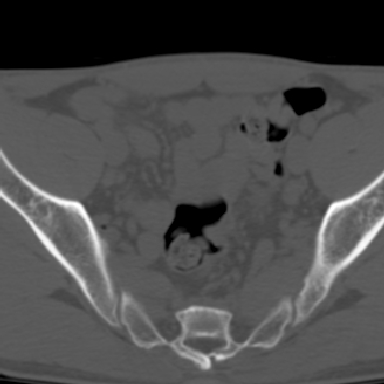

m 30 腰背部不适半年; 清晨时僵硬; 活动症状有所改善

双侧骶髂关节下2/3关节面模糊,毛糙,可见小囊状骨质破坏区.支持强直性脊柱炎.

强直性脊柱炎的早期改变!不仅表现为双侧骶髂关节,第5腰椎与骶椎间的关节突关节也有类似改变。

双侧骶髂关节下2/3关节面模糊,毛糙,髂骨侧可见小囊状骨质破坏区,骶髂关节间隙增宽(软骨破坏期)。支持早期强直性脊柱炎。

双侧骶髂关节下2/3关节面模糊、毛糙,可见小囊状骨质破坏区,呈虫咬状改变,周围可见增生硬化.支持强直性脊柱炎早期表现.

双侧骶髂关节髂骨面硬化,毛糙,小囊变,属于早期强直性脊柱炎